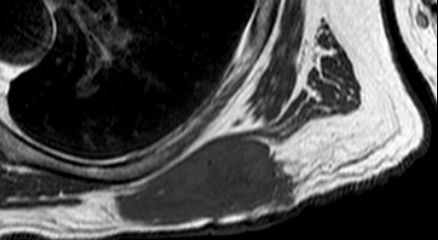

| Oberschenkel | 49-jährige Frau mit einem myxoiden Liposarkom der rechten Adduktoren-Loge.![]() |

Die enge Lagebeziehung zur A. femoralis ist gut erkennbar.![]() ![]() |